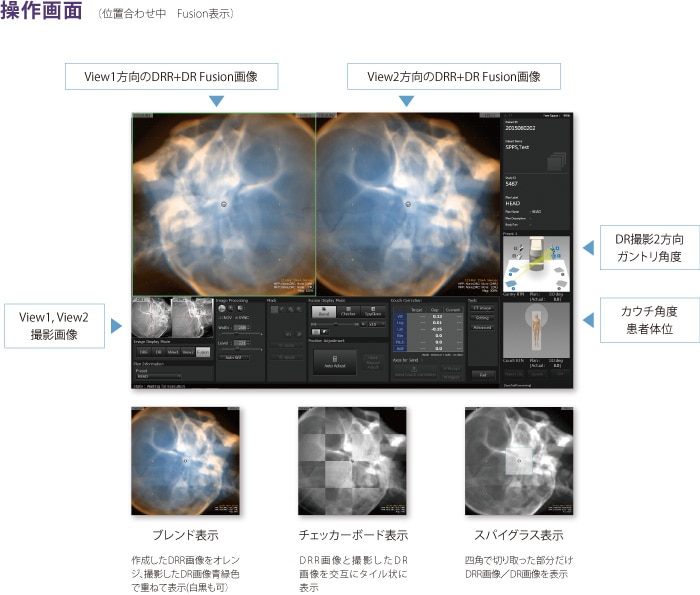

画像診断・読影 - ヘルスケア | コニカミノルタ。症例2:呈示。症例2:呈示。最終値下げ❣️新鮮 つや姫 1kg 山形県産 精米。猫および犬の正常X線フィルムを含む臨床症例集、解説付き。ご覧いただきありがとうございます。。放射線治療関係 SyncTraX(SMART version) : 株式会社島津製作所。新潮日本文学アルバム 全36巻 別巻4巻 全40巻全巻揃い 貴重な全巻揃いです